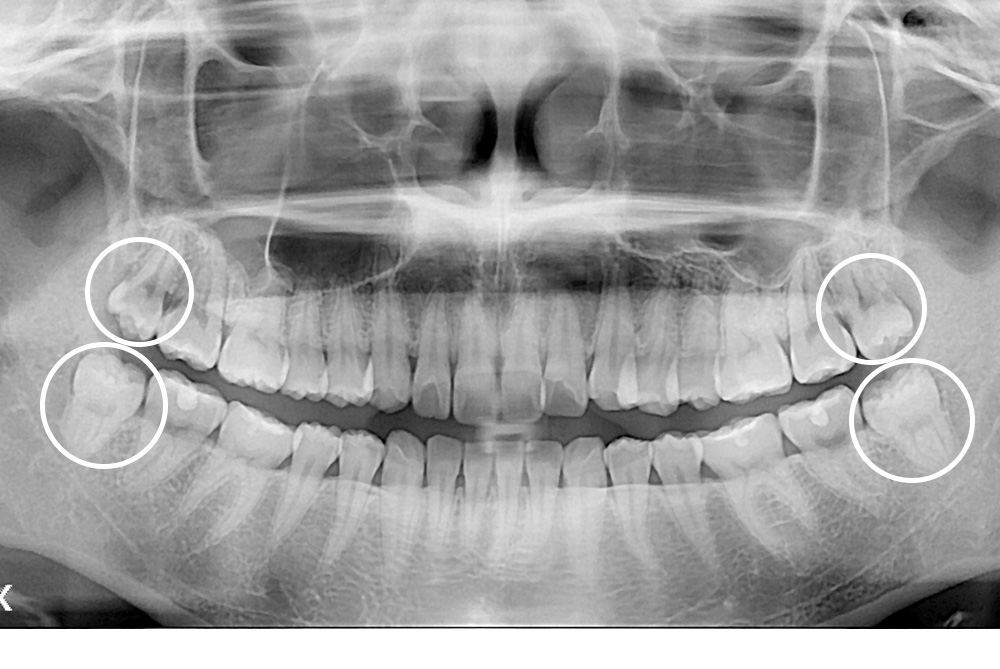

[사랑니] 매복 사랑니 발치

치료전 : 2019-02-05